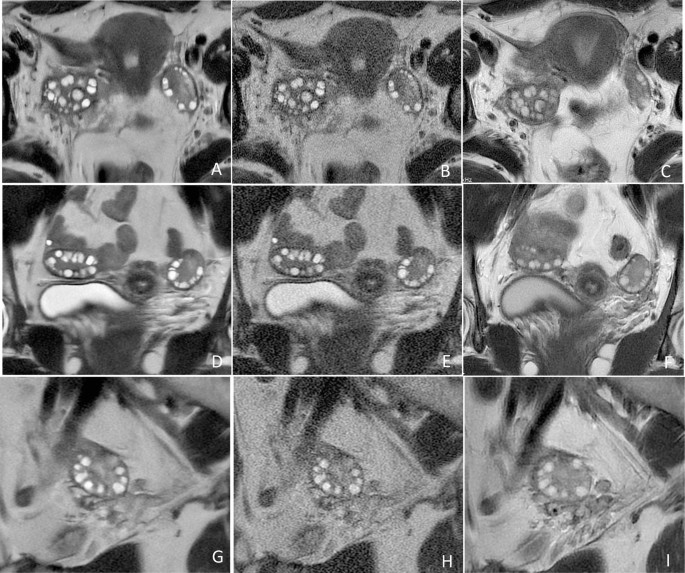

The results of the qualitative image analyses are presented in Table 2. Both observers reported significant improvements in blurring artifacts, subjective noise, and conspicuity of follicles on SSFSE-DL compared to those on SSFSE-C (P < 0.05). Notably, observer 2 reported higher scores with significant differences for the three qualitative indicators with SSFSE-DL than with PROPELLER (P < 0.05). However, the scores for subjective noise provided by observer 1 did not significantly differ between SSFSE-DL and PROPELLER. Two representative cases are illustrated in Figs. 3 and 4. The inter-observer agreements for the three qualitative items were moderate to good for SSFSE-DL (kappa, 0.575–0.723), SSFSE-C (kappa, 0.480–0.713), and PROPELLER (kappa, 0.588–0.725), respectively.

Representative T2-weighted MR images of the ovaries in a 17-year-old adolescent girl with PCOS. The SSFSE-DL images (A–G) clearly depict bilaterally enlarged ovaries and an increased number of peripheral follicles with minimal noise and blurring artifacts, providing the best conspicuity of follicles. The use of AIR Recon DL enhances the contrast between follicles and the surrounding ovarian stroma. The conspicuity of follicles in the SSFSE-C images (B, E, H) is mainly affected by noise, while that in the PROPELLER images (C, F, I) is primarily impaired by motion-related blurring artifacts.

Representative T2-weighted MR images of the ovaries in a 24-year-old woman with PCOS. The SSFSE-DL images (A, D, G) clearly show bilateral ovaries and follicles with minimal noise and blurring artifacts, providing optimal conspicuity of follicles. In SSFSE-C images (B, E, H), follicle conspicuity is primarily influenced by noise, whereas in PROPELLER images (C, F, I), it is predominantly affected by motion-related blurring artifacts.